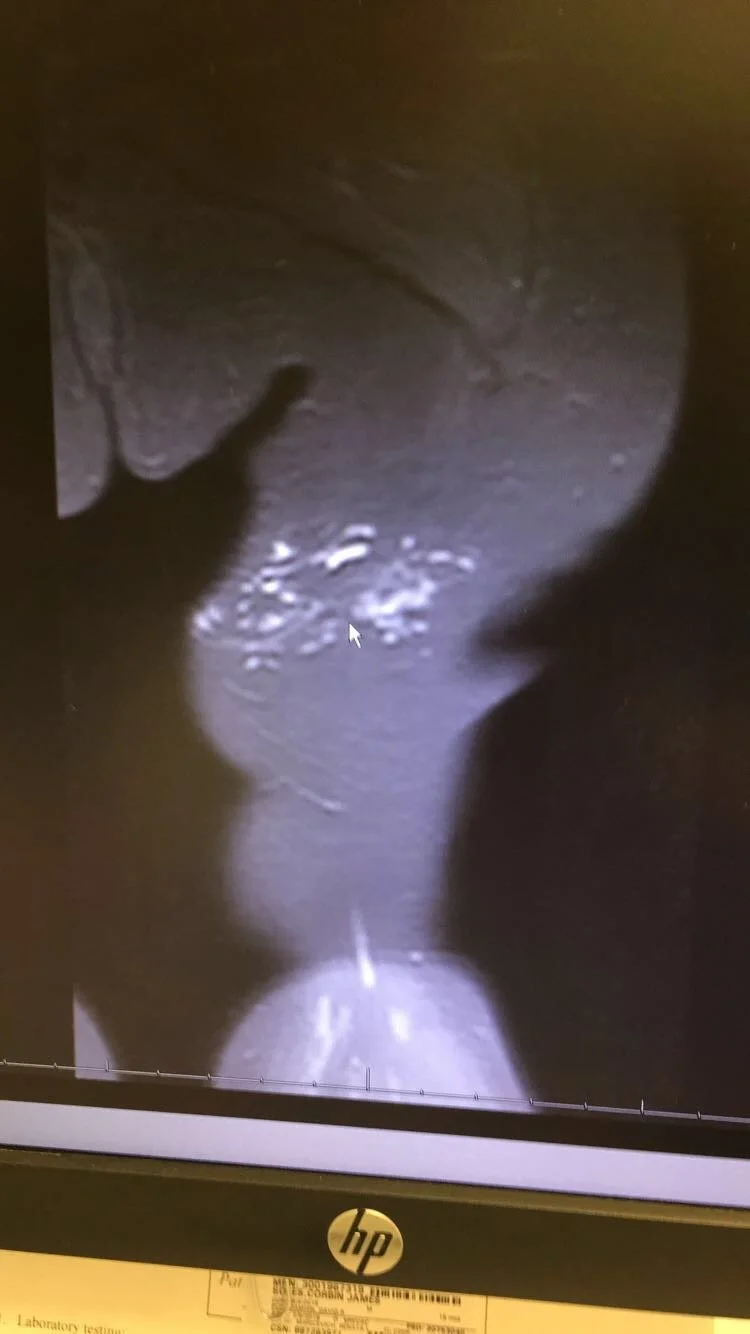

We went back for more tests. More ultrasounds. More MRIs. More waiting rooms. More unanswered prayers that turned into quiet tears.

That is when we finally got the diagnosis of lymphatic malformation.

In 2023, Corbin underwent sclerotherapy to try to shrink the cysts in his leg. They used bleomycin, a medication often used in cancer treatment. Sitting there knowing your child is receiving something that strong is terrifying, but you do it because you hope it will give them relief. It was about 60 percent successful. We celebrated that small victory even though we knew the fight was not over.